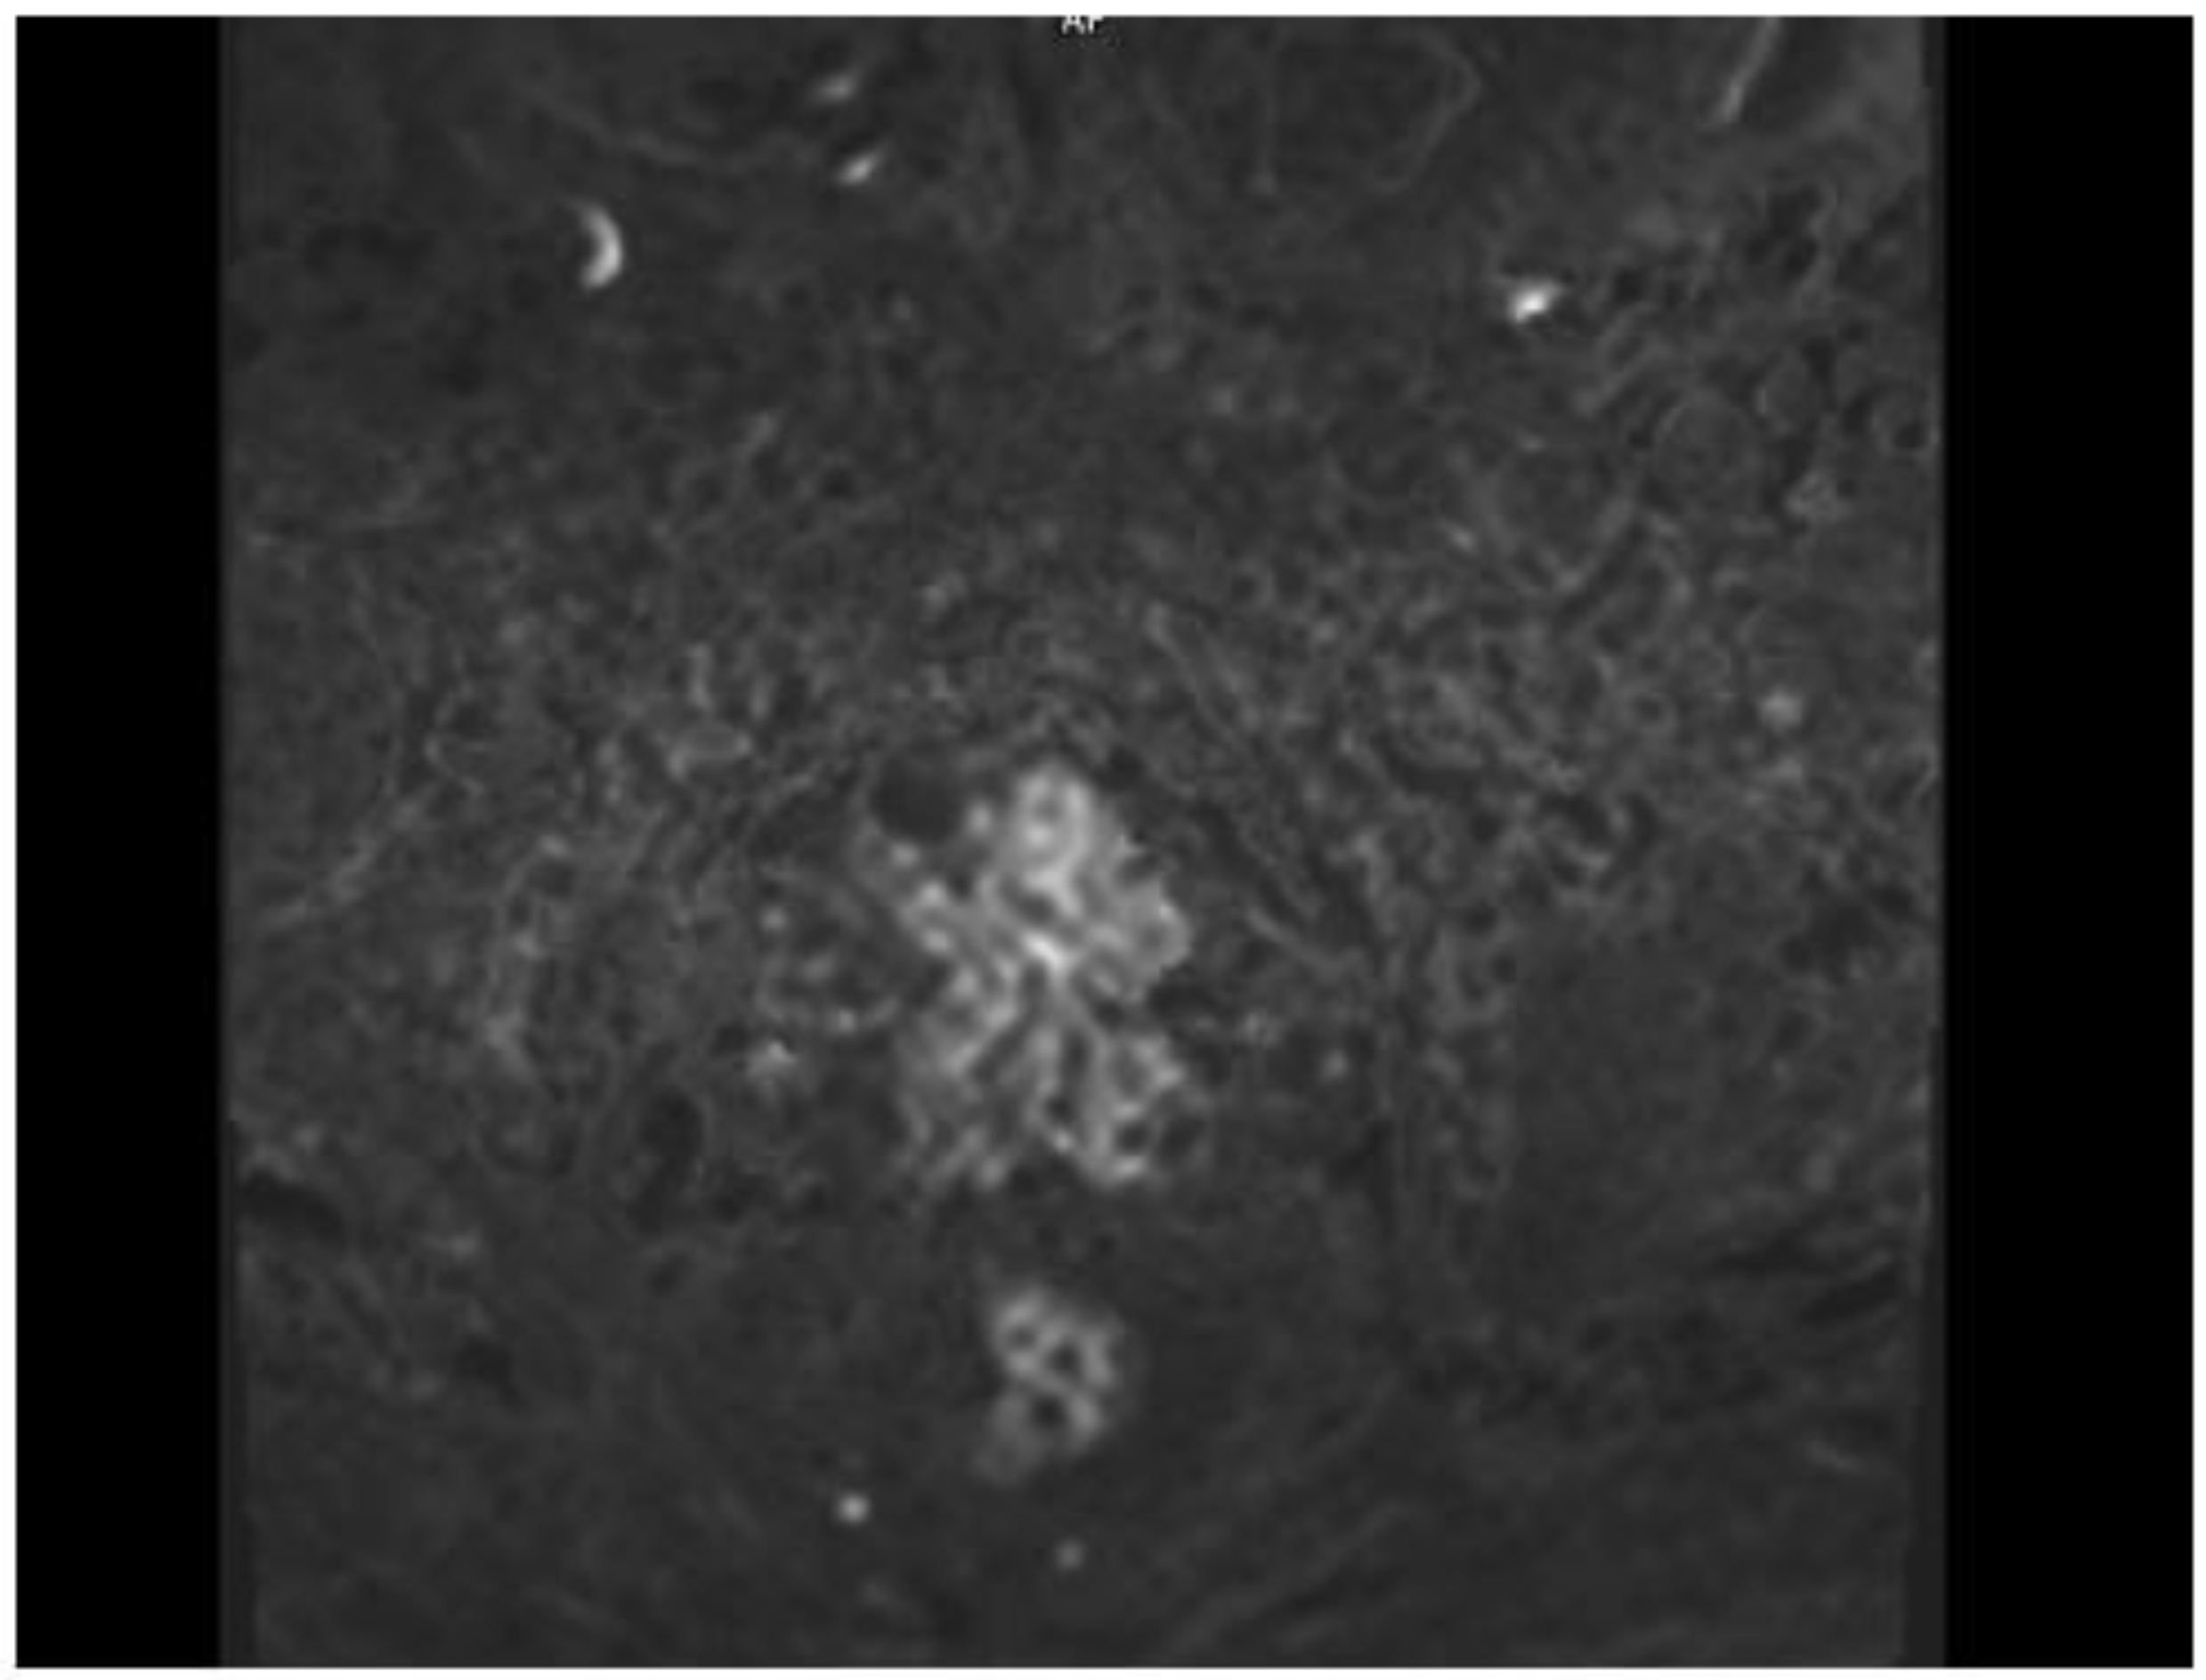

2. Case Presentation